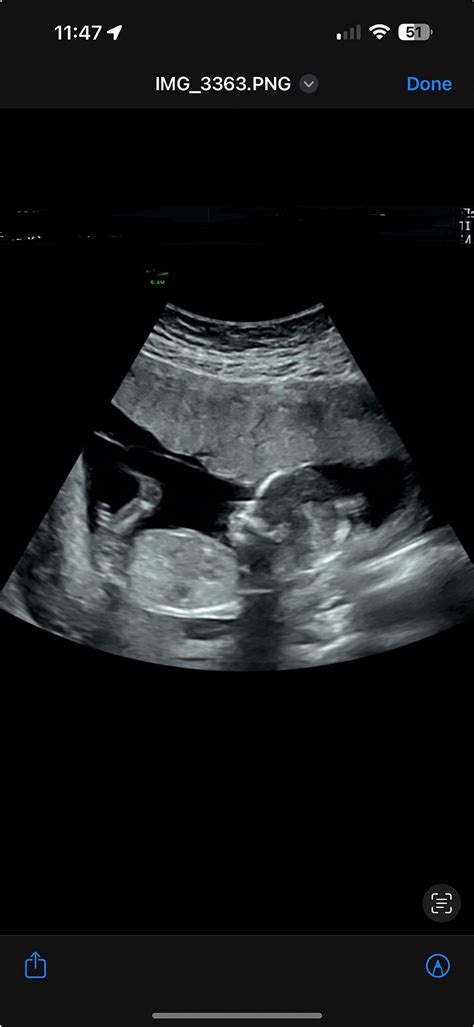

Pregnancy is an exciting journey filled with milestones, and one of the most anticipated moments is the 15 week ultrasound. This scan is a crucial part of prenatal care, providing valuable insights into the baby's development and the mother's health. Understanding what to expect during a 15 week ultrasound can help alleviate anxiety and prepare you for this important appointment.

A 15 week ultrasound is a routine prenatal check-up that uses high-frequency sound waves to create images of the developing fetus. This scan is typically performed between 14 and 16 weeks of pregnancy, but the term 15 week ultrasound is commonly used to refer to this period. The primary goal of this ultrasound is to assess the baby’s growth and development, as well as to screen for any potential abnormalities.

During a 15 week ultrasound, you will lie on an examination table with your abdomen exposed. A gel will be applied to your belly, which helps conduct the sound waves. The technician will then use a transducer to move over your abdomen, capturing images of the fetus. The entire process usually takes about 20-30 minutes.

At 15 weeks, the baby is about the size of an apple, measuring approximately 4 inches (10.1 centimeters) in length and weighing around 2.5 ounces (70 grams). The 15 week ultrasound can reveal several key features:

• Fetal Movement: The baby becomes more active, and you may see the fetus moving, kicking, and even sucking its thumb.

• Organ Development: The baby’s organs are developing rapidly. The heart beats strongly, and the lungs, kidneys, and digestive system are forming.